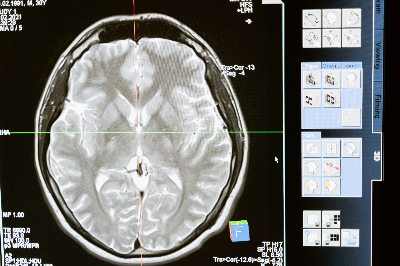

(1) 뇌하수체종양의 진단

뇌 MRI 검사가 주요 진단 방법이며 뇌하수체 부위를 정밀하게 촬영하는 뇌하수체 부위 MRI 검사를 추가로 촬영하기도 합니다. 코를 통해서 수술하는 경우가 많기 때문에 부비동 CT 검사도 시행합니다.뇌하수체 종양은 호르몬 이상이 흔하게 나타나기 때문에 혈액을 통한 호르몬 검사가 필수적이고, 시력, 시야 등의 안과 검사도 필요합니다. 코를 통해 수술하는 경우 후각 검사도 필요합니다.